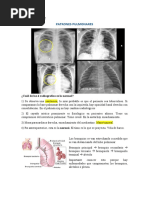

DIAGRAMA DEL LOBULILLO PULMONAR

Por definición es la última porción de parén-quima separada por tabiques. Mide

aproximadamente de 1 a 2,5 cm y contiene de 2 a 5 acinos. Para algunos autores

esta es la unidad respiratoria terminal utilizada para la correlación entre la

radiología y la anatomo-patología. Sin embargo, si consideramos que por un lado

su tamaño es muy variable y por otro que hacia el interior del parénquima hay

muy poco desarrollo de tabiques resulta generalmente muy difícil identificar e

individualizar un trastorno lobulillar.

FUNCION

El lobulillo es la unidad estructural y funcional del pulmón. Tiene forma piramidal,

su base se dirige hacia la pleura y su vértice se orienta hacia el hilio del pulmón,

es aireado por un bronquiolo y comprende todas las estructuras respiratorias

originadas de su división